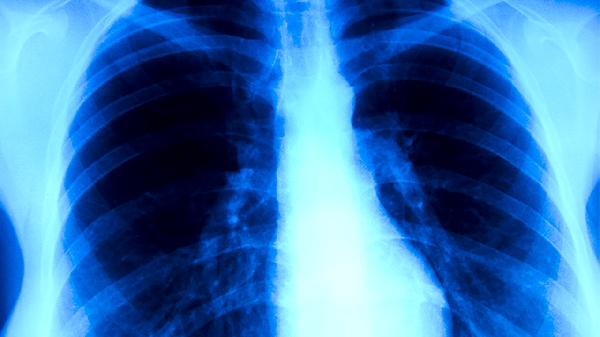

肺心病患者的表現(xiàn)是什么?

肺心病患者的表現(xiàn)主要有呼吸困難、心悸、下肢水腫、乏力、咳嗽咳痰等。肺心病通常由慢性阻塞性肺疾病、肺動脈高壓等因素引起,可能伴隨發(fā)紺、頸靜脈怒張等癥狀。建議患者及時就醫(yī),在醫(yī)生指導(dǎo)下進行規(guī)范治療。